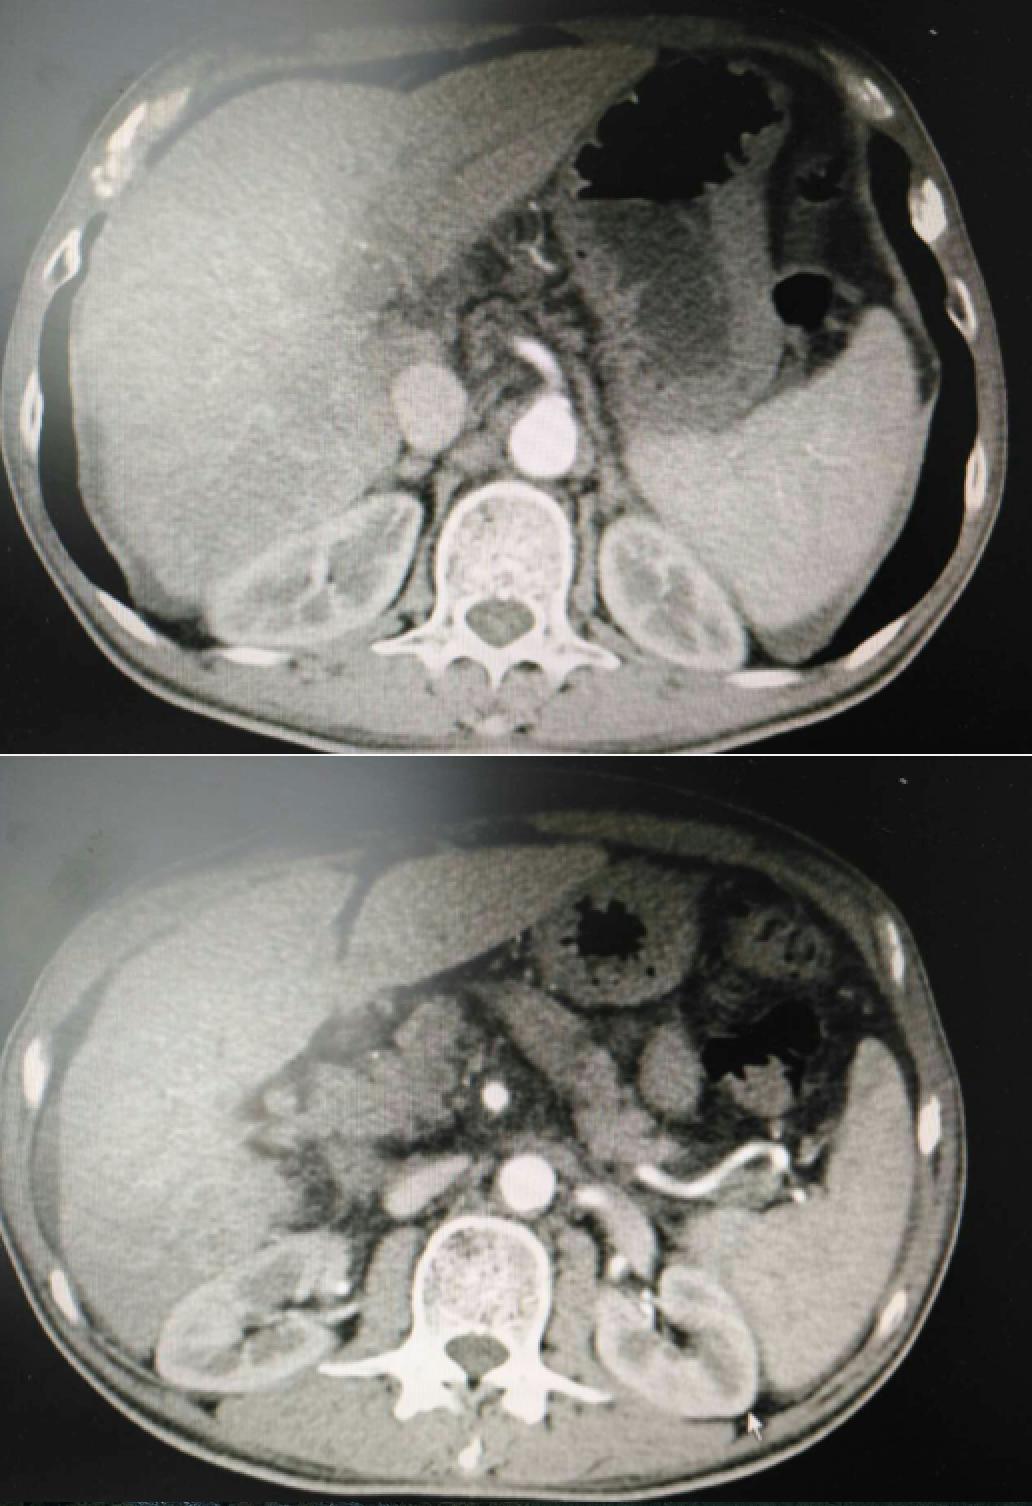

患者因纳差、烧心、腹痛、腹胀2月,于2016-01-17在某县人民医院行腹部CT示肝癌并门脉癌栓形成。分别于2016-01-22、2016-02-19于某市医院行两次TACE术(具体不详)。患者介入术后规律服用抗乙肝病毒、保肝、提高免疫力等药物治疗。2016-02-03至2016-04-30在某省立医院行5周期CIK免疫治疗。2016-05-18至2016-05-25于我院行射波刀治疗门静脉癌栓,具体放疗计划为:42Gy/7F。2016-06-24在我院行肝右动脉化疗栓塞术+肝右动脉灌注化疗术+间接门脉灌注化疗术,术中化疗总量,吡柔比星2mg、顺铂12mg、氟尿嘧啶250mg。分别于2016-05-10、2016-05-27、2016-06-13、2016-07-01、2016-07-27、2016-08-22、2016-09-19、2016-10-07、2016-10-19、2016-11-18、2016-12-18、2017-02-18行12周期免疫治疗。自2016-05-12起患者间断口服靶向药物阿帕替尼250-500mg/d,血压维持在220-130/95-70mmHg,血压升高期间伴上腹部不适,左侧为著,并向腰背部放射,偶尔反酸、烧心,剑突下疼痛,口服抑酸剂或进食后缓解,临床诊断为十二指肠溃疡,目前口服奥美拉唑、马来酸依那普利、氢氯噻嗪等药物对症降压。2017-03-02于我院行第二次肝右动脉化疗栓塞术+肝右动脉灌注化疗术+间接门脉造影术+肠系膜上动脉灌注化疗术。术中化疗总量,洛铂10mg、氟尿嘧啶500mg、吉西他滨400mg。目前间或皮下注射胸腺法新、重组人干扰素α-2b提高免疫力及慢性乙型病毒性肝炎治疗效果。

患者相关影像资料

4. 2017-3-15 DSA造影图中显示肿瘤组织血供一般,也未见癌栓显影,说明肿瘤组织或癌栓血供一般,也可能是靶向药物+栓塞化疗后,主要供血血管已闭塞,继续栓塞治疗效果有限。